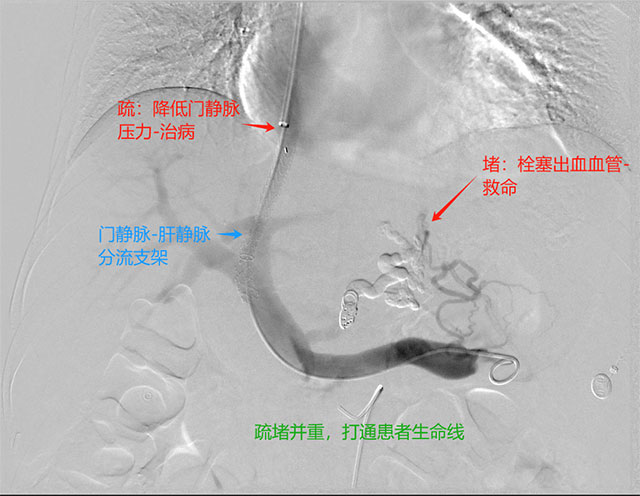

经颈静脉肝内门腔静脉分流术是外周介入中最难和风险最大的技术,是近20年发展起来的一项介入放射学治疗技术。简而言之,就是通过微创技术,栓塞出血的食管胃底曲张静脉,称之为“堵”,然后在门静脉与肝静脉支架建立一个通道,降低门静脉压力,类似于水利工程中的泄洪,称之为“疏”。疏堵并重,双管齐下,打通患者生命通道。

完善急诊术前准备后,徐燕能博士以颈内静脉为穿刺入口,将导管经上腔静脉、右心房、下腔静脉,插入肝静脉并在DSA设备的引导下由肝静脉穿刺进入门静脉内,然后扩张两者间肝实质通道后,扩张后植入专用TIPS支架在肝静脉与门静脉之间建立人工分流通道,使门静脉血流直接分流到下腔静脉,从而降低门静脉压力,达到治疗静脉曲张破裂出血、顽固性腹水等门静脉高压症的目的。